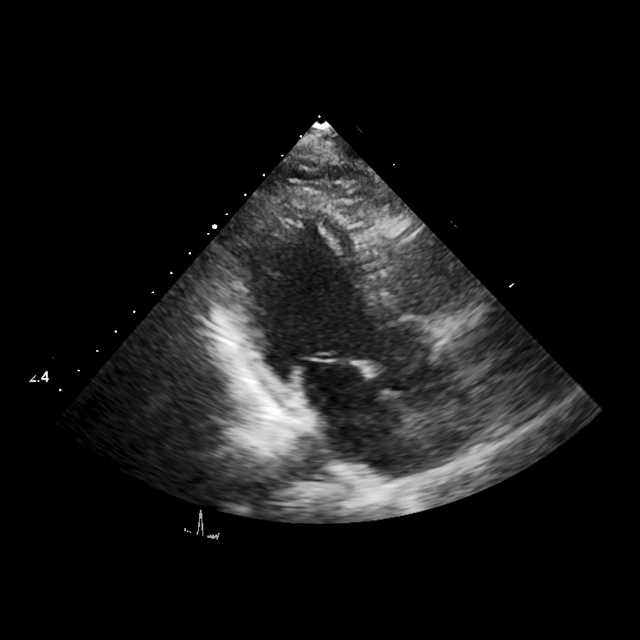

Interactive segmentation

We adapt EchoVLM for chamber segmentation tasks by attaching a prompt-based (box) encoder-decoder module following SAM (kirillov2023segment). Training and evaluation is conducted on three public benchmarks: EchoNet-Dynamic (left ventricle masks in A4C views) (ouyang2020echonetdynamic), EchoNet-Pediatric (left ventricle masks in A4C, PSAX views) (reddy2023video) and CAMUS (left ventricle and atrium masks in A2C views) (leclerc2019deep). We report Dice similarity coefficient (DSC) and compare with task-specific baselines (U-Net (ronneberger2015u) or Deeplabv3 (chen2017rethinking)), MedSAM (ma2024segment) and the vision FM EchoApex (echoapex2024).

EchoVLM outperforms tasks-specialists and achieves similar performance as vision FM. EchoVLM attains the best DSC on EchoNet-Dynamic (93.1%) and EchoNet-Pediatric-A4C (92.4%), and ties EchoApex on EchoNet-Pediatric-PSAX (93.0%) (Table 3). On the CAMUS dataset, EchoVLM matches EchoApex for left ventricular segmentation (93.8%) and achieves competitive performance for left atrial segmentation (90.2%). Visualization of segmentation results on CAMUS using EchoVLM is shown in Figure 7. These results indicate that our pretraining maintains transferable local features for segmentation across datasets.